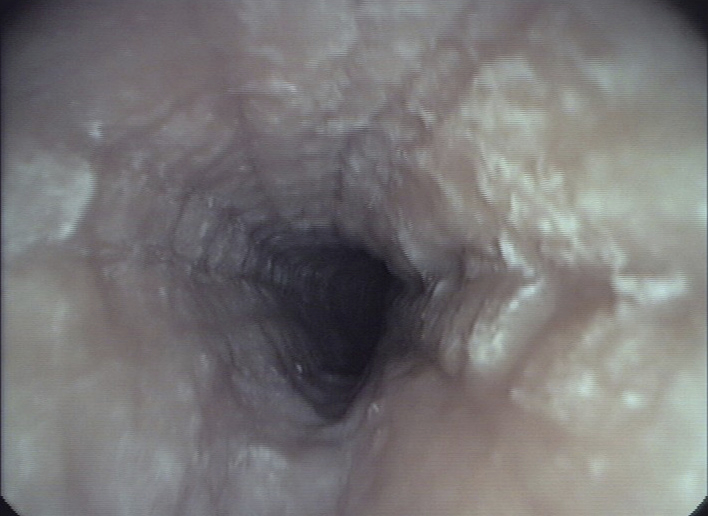

Figure 1

Endoscopic pictures illustrating the major endoscopic signs of EoE:

Panel A illustrates the endoscopic appearance of a healthy esophagus. Panel B represents a moderate inflamed esophagus with edema, longitudinal furrowing and mild non-stenosing trachealisation. Panel C shows a severe inflamed esophagus with edema, white exudates and deep furrowing. Panel D illustrate signs associated with remodeling such as stricture due to fixed esophageal rings.